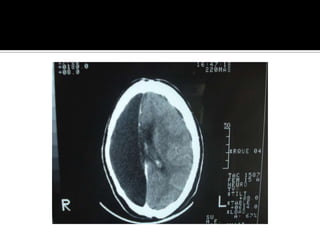

Caso clinico Mujer de 20 años , puérpera, llega a Hospital la catalogan como psicosis postparto. Dos días después coma y , después muerte cerebral. La TAC erróneamente fue interpretada como infartos lacunares.

Caso clinico Mujerde 20 años , puérpera, llega a Hospital la catalogan como psicosis postparto. Dos días después coma y , después muerte cerebral. La TAC erróneamente fue interpretada como infartos lacunares.